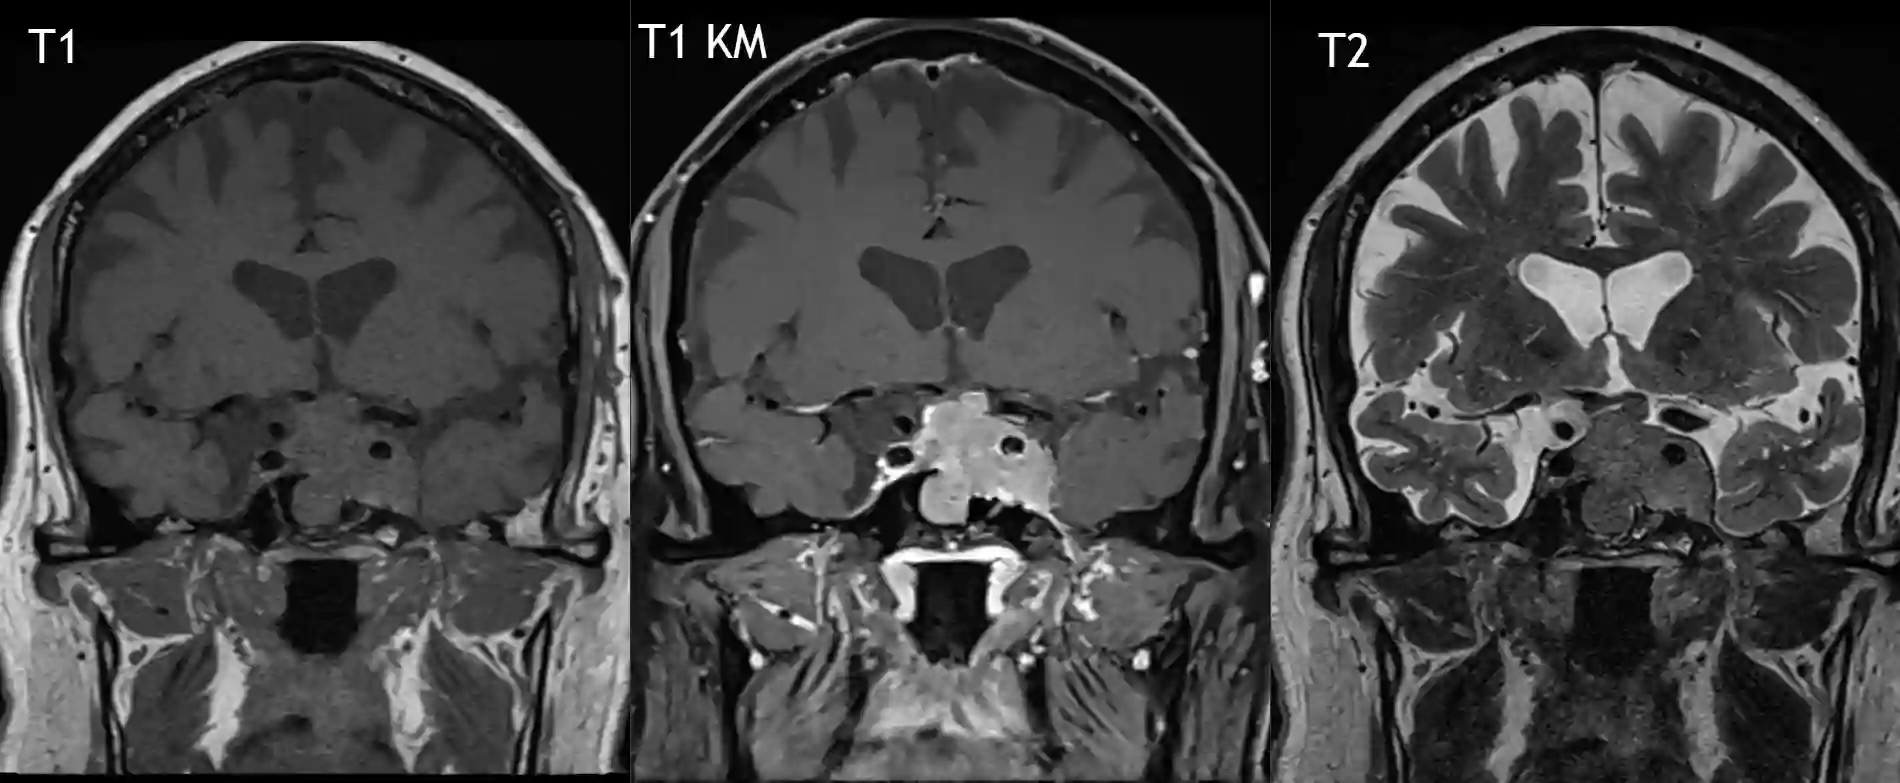

Bildgebung